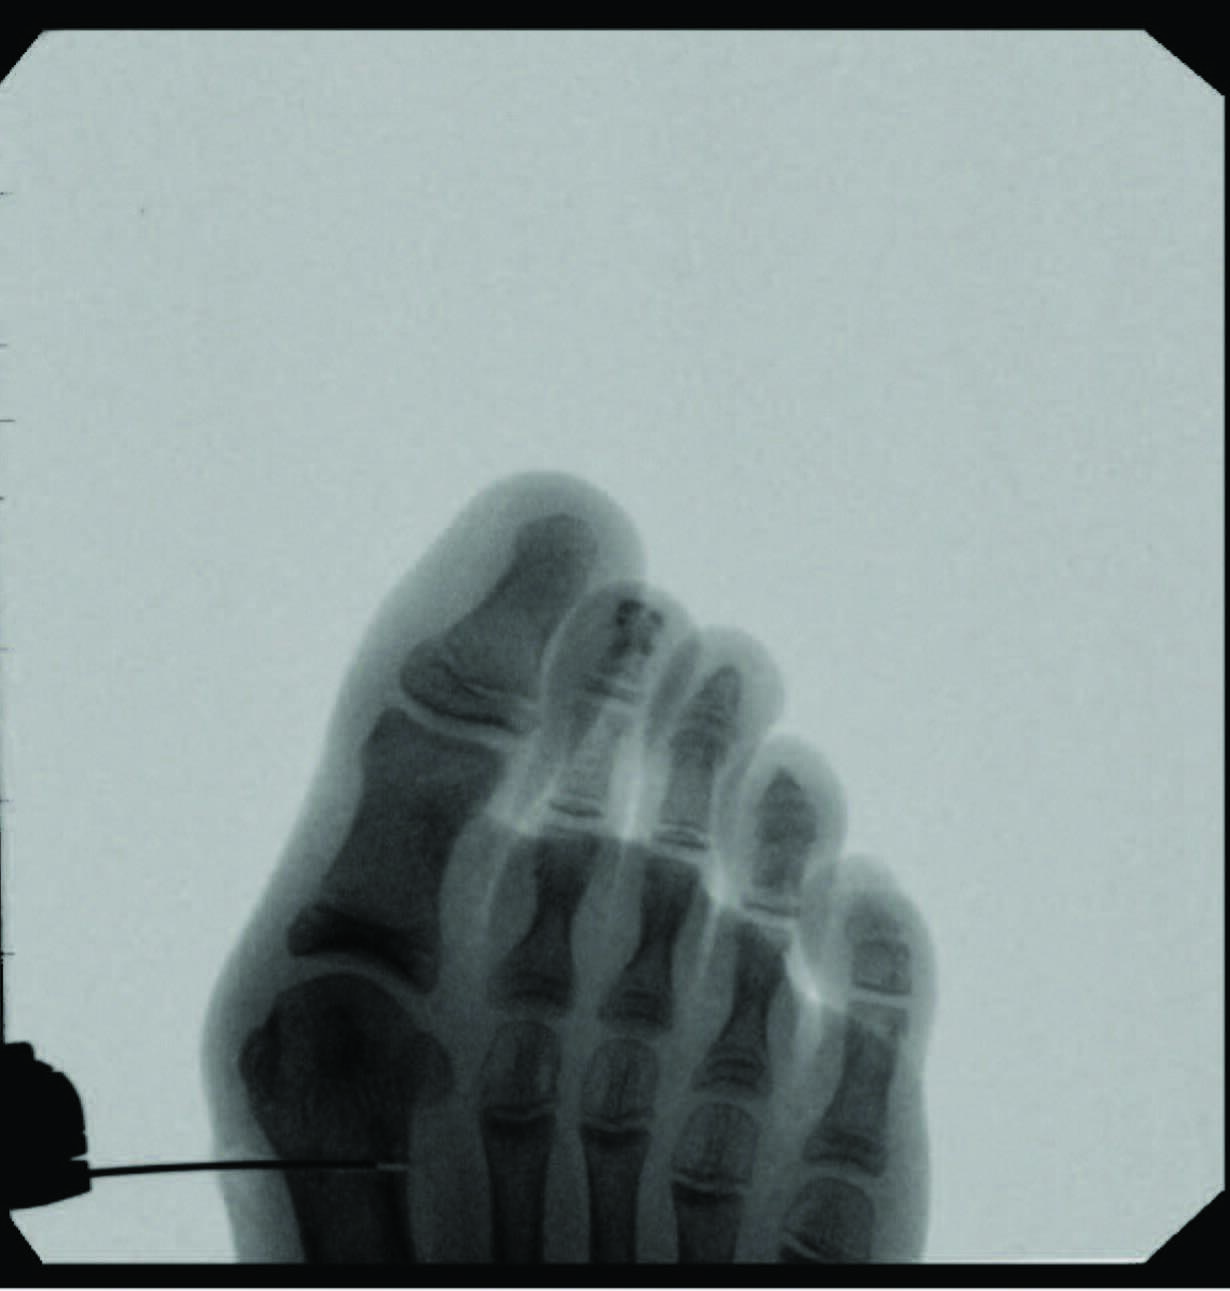

Documentation of surgical correction of hallux valgus first occurred in the early 1800s, with the earliest reports of percutaneous correction in the 1940s. Podiatric physicians experienced surgical restrictions at this time, and MIS provided an avenue for circumvention. Complications arose due to a lack of supportive means, and these outcomes led to an abrupt return to open procedures. The 1960s provided power equipment development and intraoperative fluoroscopy, which significantly improved outcomes of both open and percutaneous procedures. With the arrival of these modern tools, surgeons began to revisit the utilization of percutaneous procedures towards the end of the millennia. A subcapital osteotomy technique reported by Bosch, and “Simple, Effective, Rapid, Inexpensive,” modified by Giannini in the early 2000s, implemented a modern look at MIS hallux valgus procedures.8,9 Most recently, a guide to the percutaneous bunionectomy written by Siddiqui in 2014, and MIS radiographic outcomes in 2016, provided another available tool to surgeons, which decreased the complication rates and expanded the confidence in utilization of MIS bunion correction universally.10

One can allow early mobilization by immediate weight-bearing in the postoperative course, most notably providing a decrease in adhesions and consequent stiffness of the joint. Another advantage includes multiple viable fixation options, including splintage with a Steinmann pin through external fixation. Many long-term risks of internal fixation include foreign body reaction, growth disturbance, chronic infection, corrosion, implant migration, and potential interference in orthopedic treatment later in life.14 Schmittenbecher and coworkers described risks of implant removal in children with various fixation options, concluding that each patient’s treatment selection must weigh the benefits and risks.14 Steinmann pin fixation may, in my experience, alleviate these risks, removing it around four weeks postoperatively.

Some surgeons hypothesize that the lack of lateral capsular or tendon balancing procedures allows an increase in soft tissue tension to provide stability to the capital fragment of a construct that is not inherently stable. Common complications include relapse or malalignment, where the capital fragment achieves excess dorsiflexion or plantarflexion. The most common complication reported by some is pin site infection at 19.4 percent, successfully treated with oral antibiotics.10